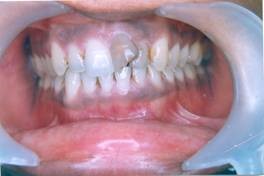

Our Treated Happy Patients